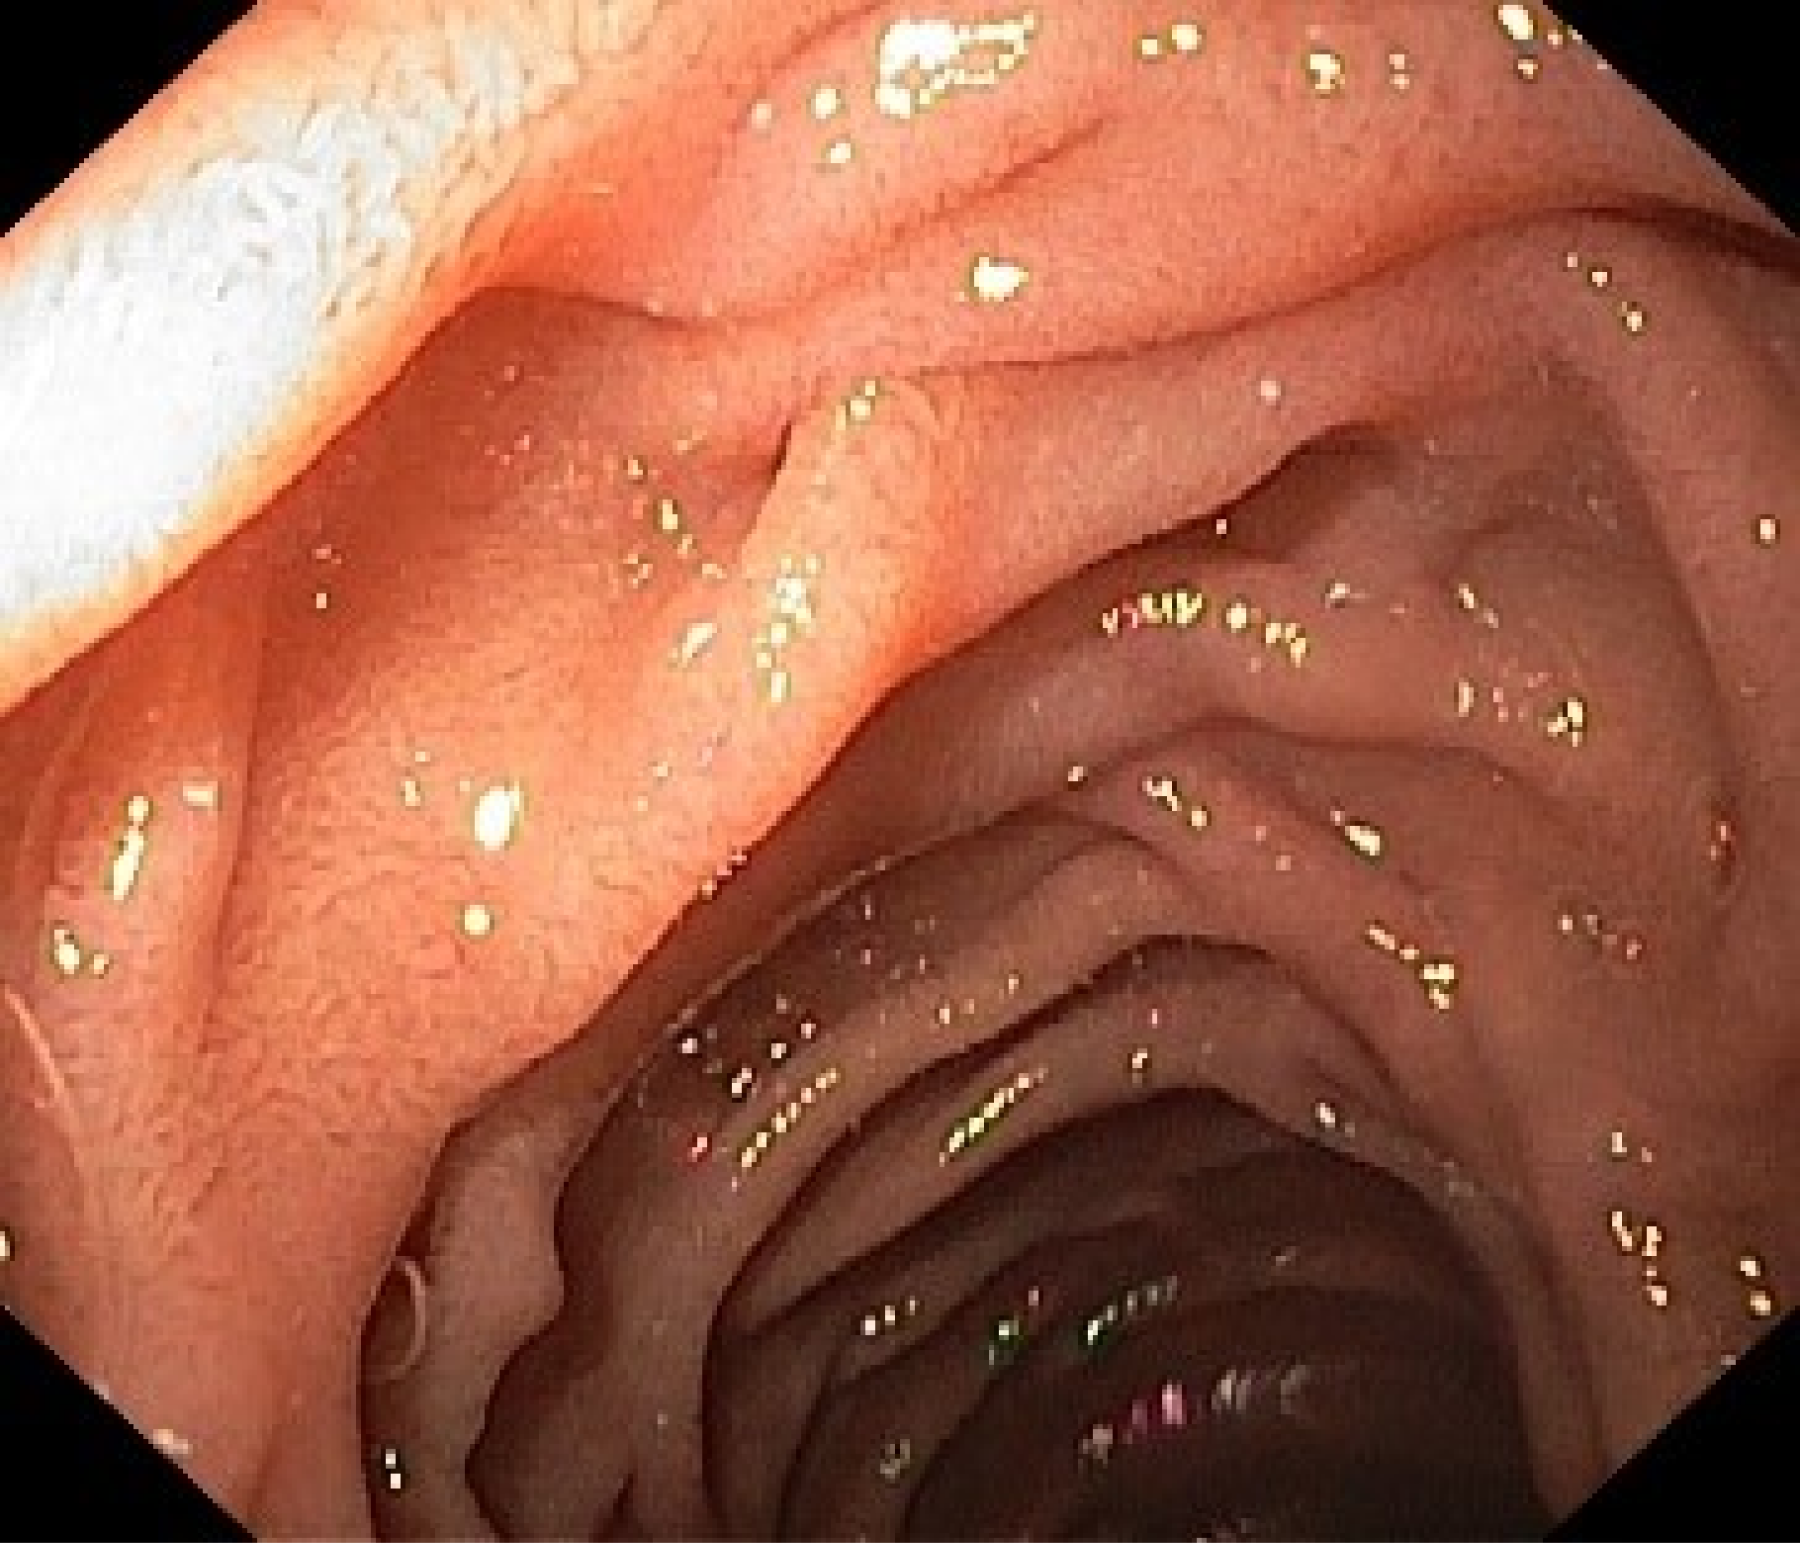

📸✨ Мы рады представить вам результаты улучшения качества нашего эндоскопического оборудования! На фото вы можете увидеть сравнение желудка, снятого на новом и старом аппарате. Разница действительно впечатляет!